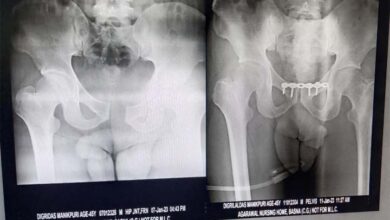

बसना: सड़क दुर्घटना में टूट गया था कमर की हड्डी,अग्रवाल नर्सिंग होम के टीम डॉ. संदीप सराफ ने हड्डी को जोड़ा

बसना: अग्रवाल नर्सिंग होम बसना के चिकित्सकों के सराहनीय प्रयास से डिग्री दास मानिकपुरी ग्राम बरोली का कमर की हड्डी…